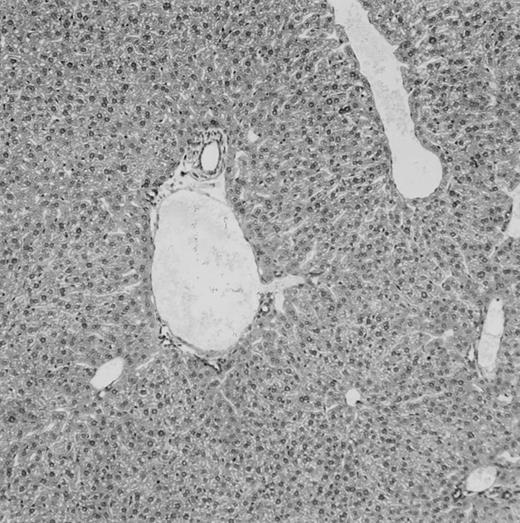

Histologic findings. Organs were collected at different times after BMT and tissue sections were stained with hematoxylin and eosin. Original magnifications for spleen (left) and liver (right) are ×40 and ×100, respectively. (A) B6 mice receiving FVB BM plus EpTK T cells. (B) Control group receiving BM only.

(C) B6 mice receiving FVB BM plus EpΔTK T cells and treated with GCV. (D) B6 mice receiving FVB BM plus EpΔTK T cells, treated with GCV, and developing a late onset GVHD (day 54).

FVB BM-grafted B6 mice: a model of lethal GVHD.We developed a model of GVHD resulting in 100% mortality soon after BMT using FVB mice, a strain not previously used as BM donors in experimental allogeneic BMT. We tested different combinations of recipient irradiation doses, as well as injected BM cell and CD3+ peripheral T-cell numbers. When 10-Gy–irradiated B6 mice were reconstituted with 107 FVB BM cells, we observed prolonged survival, whereas all ungrafted animals died before day 16 (Fig 2). In these conditions, more than 98% of splenocytes were of donor origin (Fig 3A). When 107 CD3+ peripheral T cells from mice of FVB genetic background were added to the FVB BMT, all animals died of GVHD between days 7 and 34 (Fig 2). Similar results were obtained using either PBS-treated mice receiving EpTK or EpΔTK peripheral T cells or GCV-treated mice receiving FVB nontransgenic peripheral T cells. Notably, this observation also indicates that both TK- and ΔTK-expressing T cells in the absence of GCV are fully competent to induce a lethal GVHD. Histopathologic examination of spleen and liver of these animals showed characteristic GVHD lesions such as (1) architecture disruption, necrosis, and congestion in the spleen; (2) hepatic periportal necrosis; (3) mononuclear portal infiltrates; and (4) endothelialitis of portal or centrolobular veinules (Fig 4A). By comparison, B6 mice receiving only FVB BM had a normal histology (Fig 4B).

Using this delivery mode, we observed that mice receiving a 7-day GCV treatment initiated at the time of transplantation were protected from GVHD. At day 60, the survival rate was 100% in the GCV-treated group receiving EpTK CD3+ T cells, and was still 92% at the end of a 120 day follow-up (Fig 2A). Protected mice were apparently healthy, presented no visible skin lesions, and gained weight comparably to controls receiving only BM (data not shown). Hematologic reconstitution was analyzed by flow cytometry at different times from day 14 to day 212. Splenocytes of GCV-treated animals were of donor H-2q origin in the B-cell (B220+) and non–B-cell (B220−) compartments, the latter containing donor Thy1.1+ T cells but no recipient Thy1.2+ T cells (Fig 3B). Finally, histological analysis in these animals showed nodular architecture in the spleen and no significant hepatocyte necrosis or portal mononuclear cell infiltrates in the liver (not shown) and similar to control animals receiving only BM. Taken together, these data indicate that a GCV treatment, administered at the onset of allogeneic BMT and with a course as short as 7 days, abrogates GVHD and allows a full recovery from the lethal irradiation.